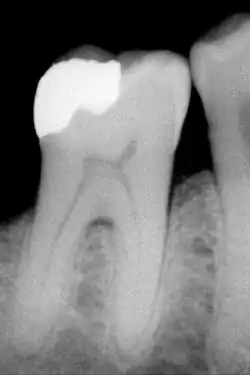

B) Röntgenologische Diagnostik

Als Approximalkaries bezeichnet man eine Karies, die an den Kontaktstellen nebeneinander stehender Zähne, demnach im Zahnzwischenraum, entsteht.

Die Präsentierung von Karies ist sehr variabel, allerdings sind die Risikofaktoren und Stadien der meisten Erscheinungsbilder identisch. Je nach Lokalisation ist die Karies entweder direkt sichtbar, oder kann erst durch diagnostische Werkzeuge (Röntgen, Sonden, Laser) sichtbar gemacht werden.[11] Die primäre Diagnosestellung beim Zahnarzt erfolgt in erster Linie durch Inspektion mit einer starken Lichtquelle, einem zahnärztlichen Spiegel und einer Sonde in Kombination mit Druckluft. Die Ergebnisse der Inspektion werden mit Röntgenbildern verglichen, die Karies in den nicht-zugänglichen Bereichen der Zähne (Fissuren, Kontaktpunkte zwischen den Zähnen) sichtbar machen können. Hierzu werden Bissflügelaufnahmen angefertigt.[12] Der Einsatz von Sonden zur Kariesdiagnose, insbesondere solcher mit spitzen Enden, wird in der Fachliteratur kontrovers diskutiert.[13] Karies im frühen Stadium kann durch den Einsatz von Fluoriden gestoppt werden, solange sich noch keine Kavität gebildet hat. Solche Bereiche könnten durch spitze Sonden einbrechen, wodurch die erkrankte Stelle nicht mehr allein durch Fluoridierung remineralisiert werden kann.[14]